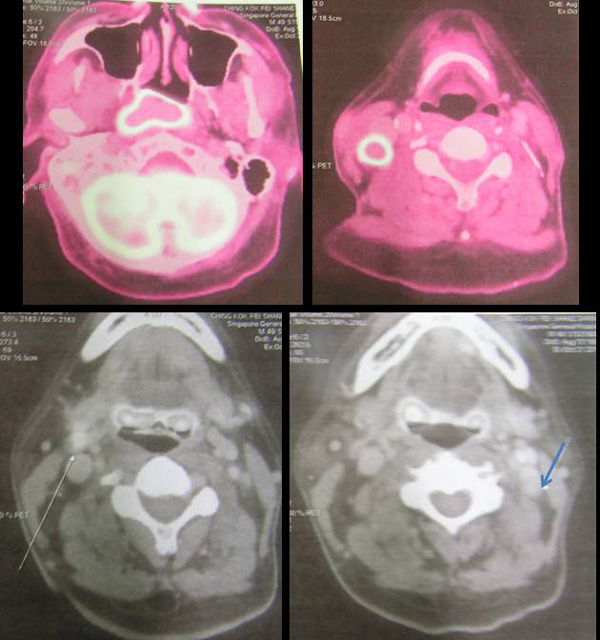

Danny is a pastor of a church in Singapore. He is 48 years old. Sometime in early August 2011, he had dengue.  His right cheek was swollen and his ear was blocked. His problems resolved after hospitalization. However, a PET scan done on 21 October 2011 revealed the following:

1. FEG-avid right nasopharyngeal mass. There is effacement of the right parapharyngeal space and extension across the midline.

2. Hypermetabolic right retropharyngeal, right level 2 and 3 adenopathy.

3. Necrotic enlarged left FDG-avid level 2 adenopathy.

Impression: Right nasopharyngeal  tumour. There is also right retropharyngeal adenopathy, left level 2 cervical node and right level 3 node.

A biopsy was performed and confirmed cancer of the nasopharynx, T2N2Mo.

Pastor Danny subsequently underwent chemotherapy and radiotherapy. He successfully completed 33 sessions of radiation but managed to complete only 2 cycles of chemotherapy (scheduled for 6 cycles). The chemo-drug used was cisplatin.